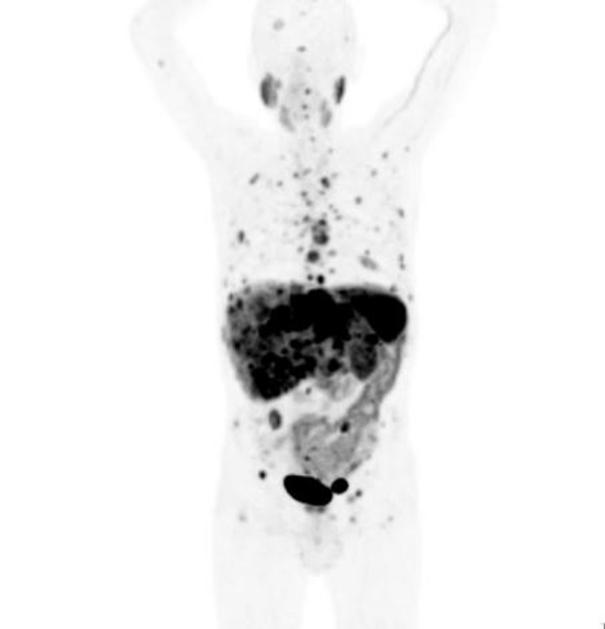

Izdelava radioaktivnega zdravila

UKC Ljubljana: Izdelava radioaktivnega zdravila UKC LJ UKC Ljubljana: Izdelava radioaktivnega zdravila